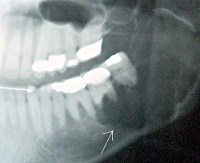

C41.1 Злокачественное новообразование нижней челюсти